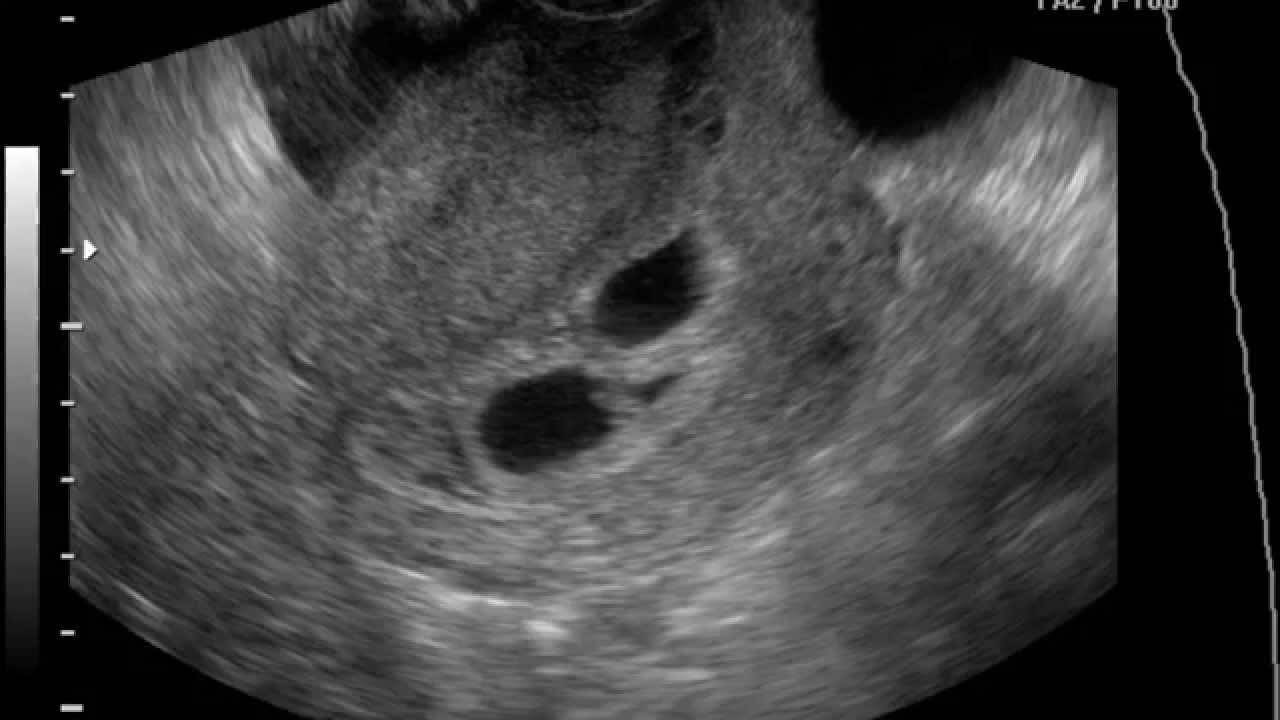

- Отслойку плаценты легкой формы – никак себя не проявляет и выявляется только в момент проведения УЗИ или уже после родов, когда врачи замечают небольшую впадину с темными кровяными сгустками на детском месте.

- УЗИ;

- Легкая степень характеризуется преждевременной отслойкой небольшого фрагмента плаценты. При этом общее состояние беременной практически не изменяется. Ультразвуковое исследование может показать наличие ретроплацентарной гематомы, однако если имеют место небольшие выделения из половых органов, то ее не будет. После родов на плаценте образовывается небольшой сгусток.